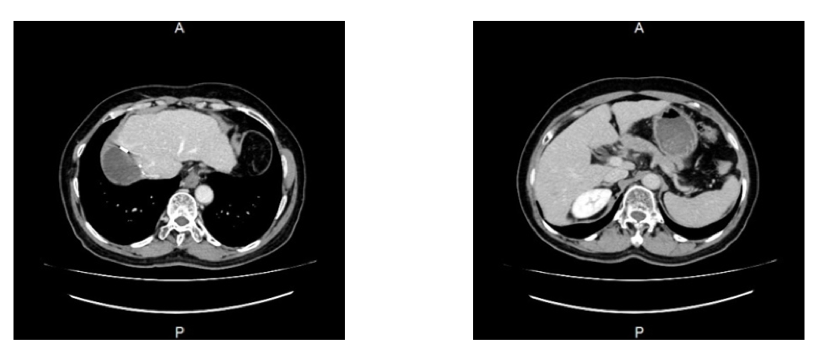

更换二线治疗后,2022年4月21日复查。检验结果:血常规,凝血功能、肝肾功基本正常;乙肝两对半:HBsAg、HBcAb阳性;AFP:10.1ng/mL↑。上腹部CT增强:右肝癌 TACE 肝复发肿瘤切除术后改变。

术后2021年4月21日行复查上腹部CT增强提示:右肝癌 TACE 肝复发肿瘤切除术后改变,现术区肿胀、渗出及腹腔积液,均较前明显吸收(图5)。

图5.2021年4月21日行复查上腹部CT

瑞戈非尼作为国内外权威指南一致推荐的高循证级别二线治疗药物[1-3],其良好的疗效与安全性在该病例中再次得到验证。2022年4月21日复查显示,该患者病情控制良好,疗效评估达部分缓解(PR),提示在中晚期肝癌一线治疗后进展的患者中,应用免疫联合二线靶向治疗药物瑞戈非尼可控制肝癌的发展,延长患者的生命。在治疗过程中未发生明显的不良反应,如胃肠道反应、高血压等,且目前患者仍在持续用药并获益中。该病例为这一治疗方案提供了有价值的经验线索。事实上,在临床治疗中我们已有诸多肝癌患者一线治疗进展后,采用瑞戈非尼二线治疗后取得了良好的治疗效果,期待后续更多病例的积累,以带来更多数据与证据。